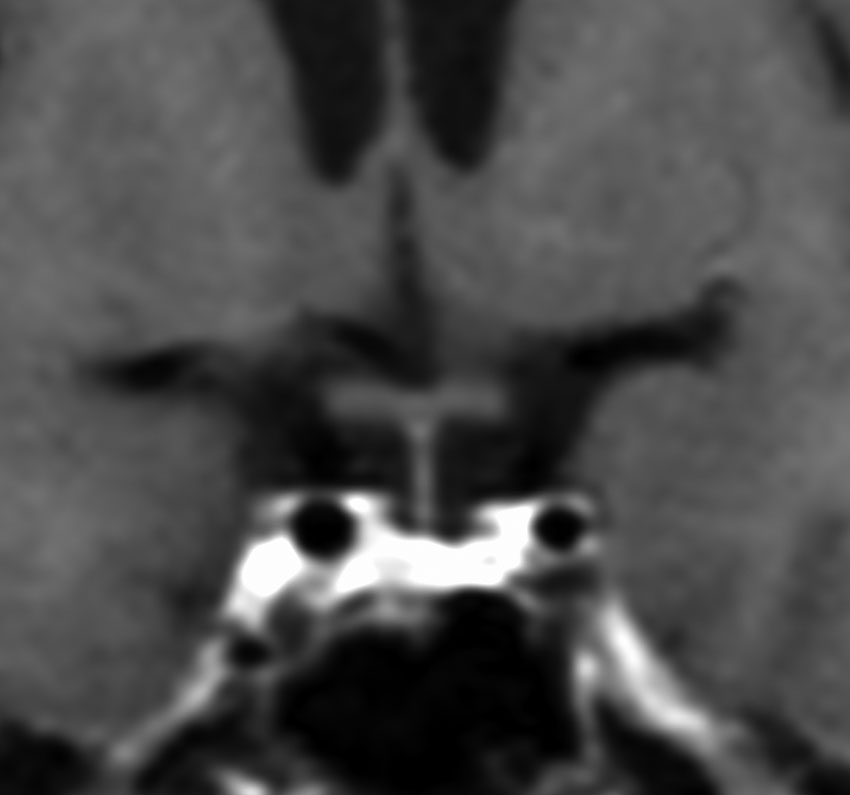

この例は18歳,HCG 0.1mIU/ml,尿崩症で発症しました。神経下垂体ジャーミノーマなので,下垂体前葉のみが残って後葉から視床下部が腫瘍化しています。よくよく見ると松果体にもごく小さな腫瘍があります。右のCISS画像で松果体の腫瘍化が明瞭です。

経鼻生検術で下垂体後葉部分がgerminomaということを確認してからICE (IFO/CDDP/VP-16)を1コース加えて3週間後の画像です。腫瘍は灰白隆起の部分を残してほぼ消失しています。松果体部の腫瘍も消えています。典型的なgerminomaの化学療法反応性を示しています。下垂体前葉機能は正常,尿崩症も少し良くなりました。